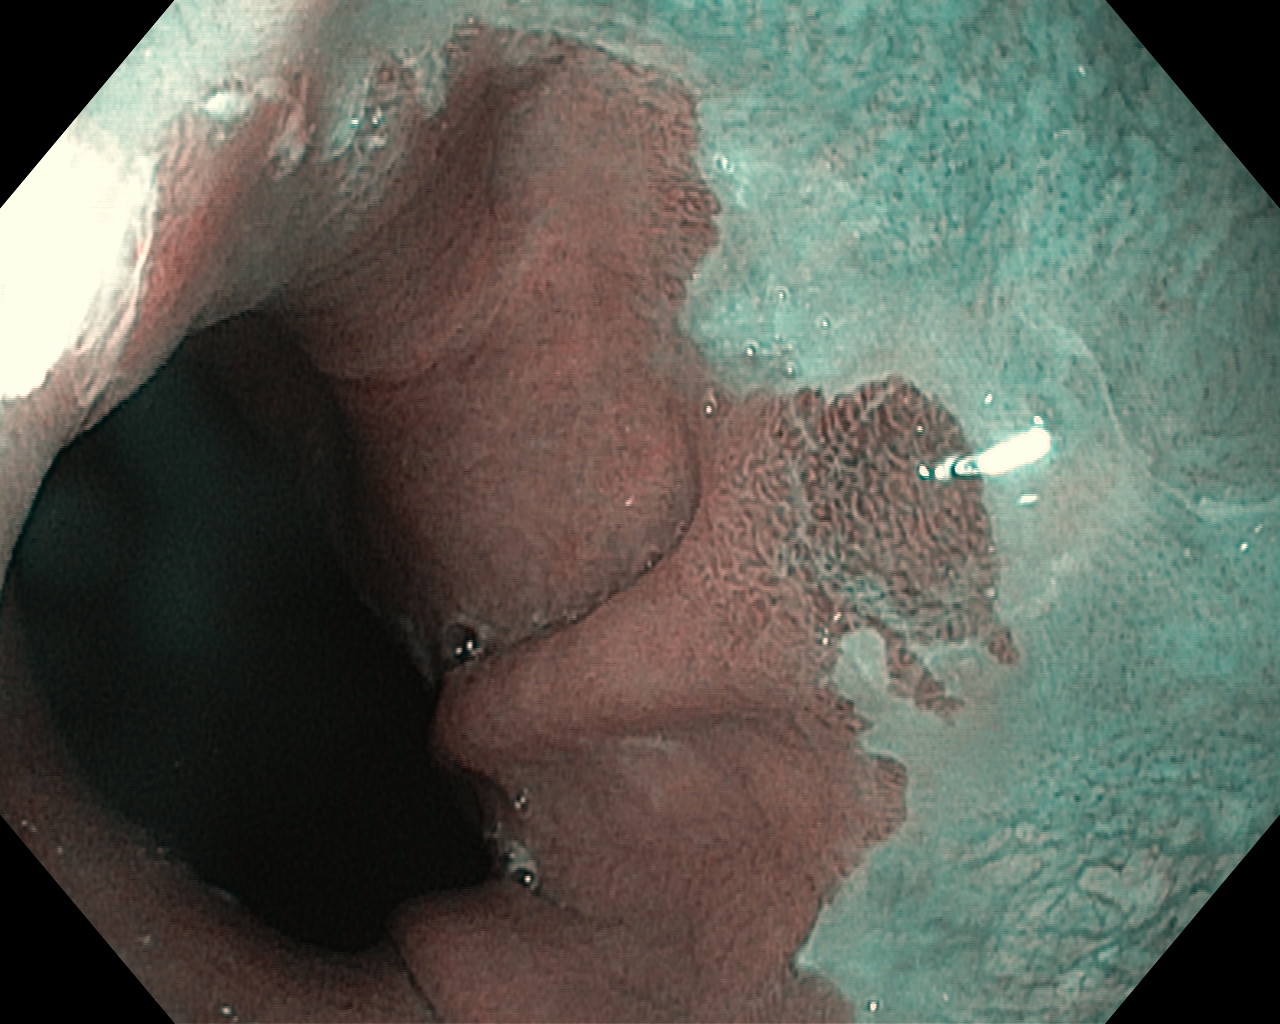

Przełyk Barretta